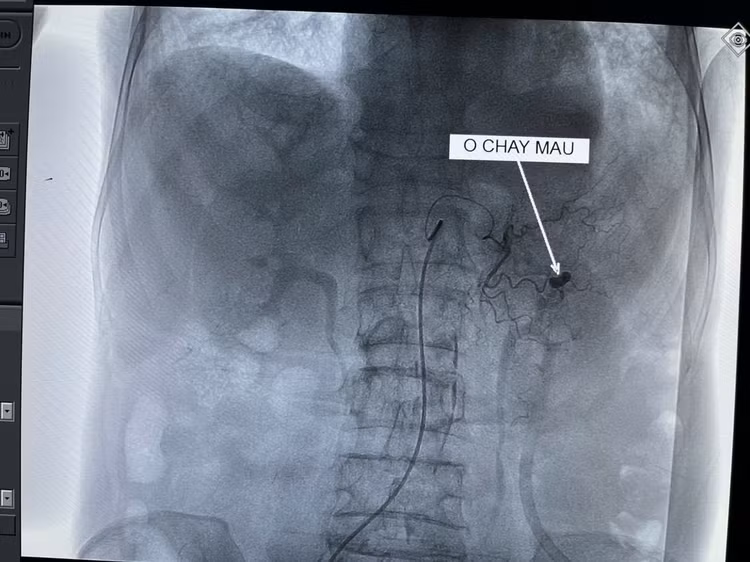

Ổ chảy máu trên màn hình - Ảnh BVCC

Qua chụp CT tiêm thuốc cản quang và chụp mạch trên máy DSA, thấy được vị trí chảy máu dạ dày tương đối lớn. Các bác sĩ đã tiến hành nút tắc toàn bộ nhánh động mạch chảy máu. Sau can thiệp, chụp kiểm tra lại, hệ thống động mạch không còn điểm chảy máu nào khác trong ống tiêu hóa.